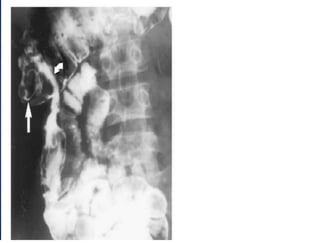

• Barium studyXray (barium enema or barium follow through x- ray) — Pulled up caecum, conical caecum, pulled down hepatic flexure — Obtuse ileocaecal angle; straightening (Goose neck) — Steirlin sign: Hurrying of barium due to rapid flow and lack of barium in inflamed site — Fleischner sign (Inverted umbrella sign): Narrow ileum with thickened ileocaecal valve — Napkin leisons- ulcers and strictures in the terminal ileum — Increased transient time:Hypersegmentation(chicken intestine) — Mega Ileum: Dilatation of proximal ileum

Barium enema: • increased(obtuse) ileocaecal angle • retracted, fibrosed caecum ("goose neck deformity") ;

Ileocecal tuberculosis. Radiograph obtainedwith peroral pneumocolon technique demonstrates a conical and shrunken cecum (straight arrow) retracted out of the iliac fossa by contraction of the mesocolon. Note also the narrowing of the terminal ileum (curved arrow).